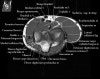

팔꿈치 관절의 MRI 단면 영상

- Sagittal section

1) Biceps Brachii tendon and Brachiallis muscles

2) Radial head for radiographically occult fractures

3) Distal Triceps tendon